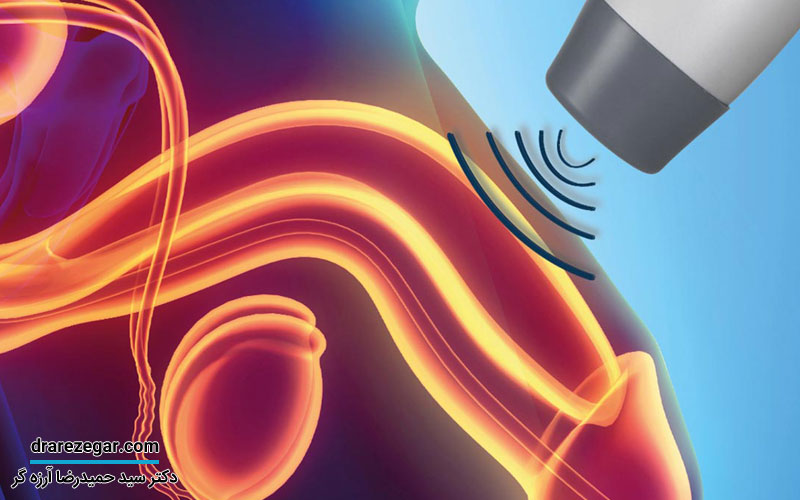

تشخیص عفونت مثانه معمولاً از طریق آزمایش های تشخیصی مانند آزمایش ادرار، سیستوسکوپی و سونوگرافی صورت می گیرد. درمان این نوع عفونت معمولاً شامل استفاده از داروهای ضد باکتری و داروهای ضداسپاسم است. با درمان به موقع، انتظار می رود که عفونت در کمتر از دو هفته بهبود یابد، اما بازگشت عفونت نیز امری شایع است. درمان ناکافی می تواند منجر به عفونت مزمن مجاری ادرار و در نهایت نارسایی کلیه شود. بیماری هایی مانند عفونت های غدّه پروستات و تشکیل سنگ ها در مثانه نیز اغلب با عفونت مثانه همراه هستند.